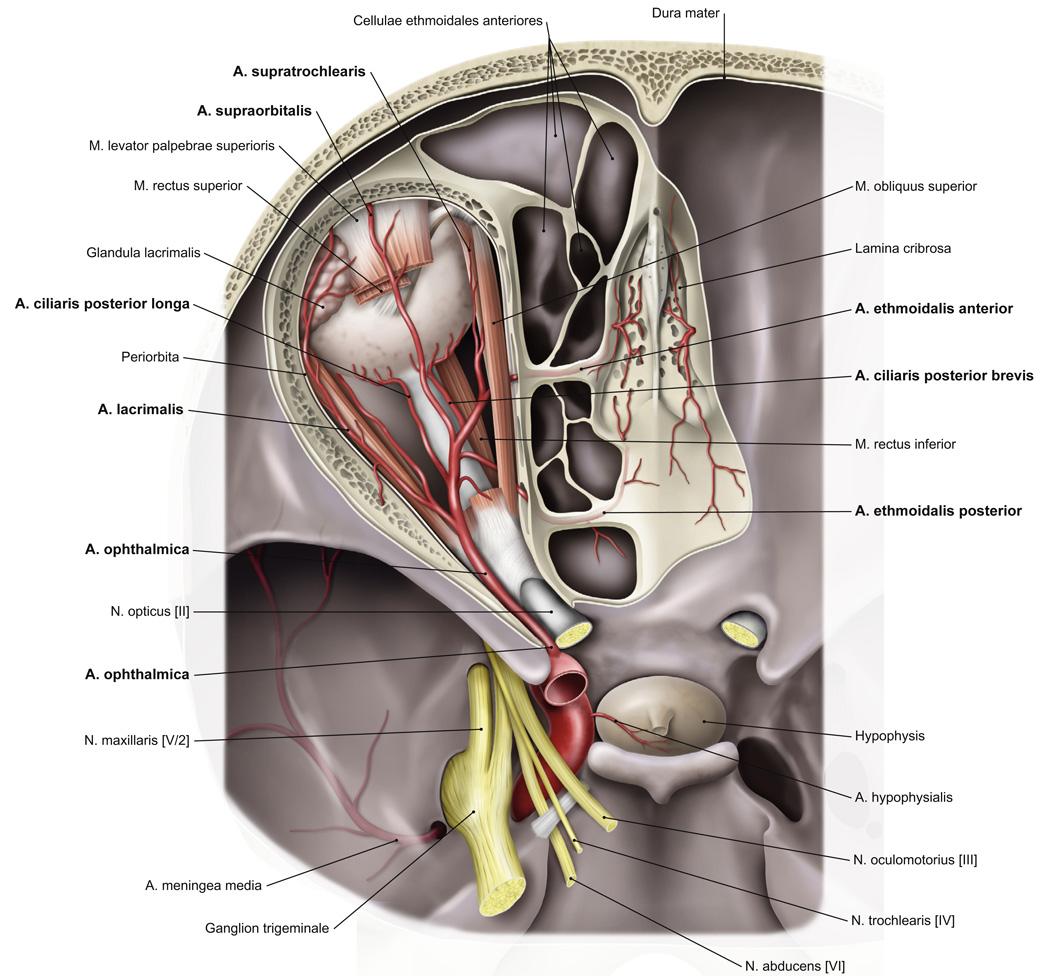

Fig 3.12: a. ophthalmica

orbita canalis n. opticus n opticus + retina (groen) a centralis retina (in n. opticus) a lacrimalis takken oogbol a supraorbitalis (via foramen/incisura supraorbitalis naar huid) a ethmoidalis posterior (via foramen ethmoidale posterius naar neus) a ethmoidalis anterior (via foramen ethmoidale anterius naar neus) -

eindtakken

|